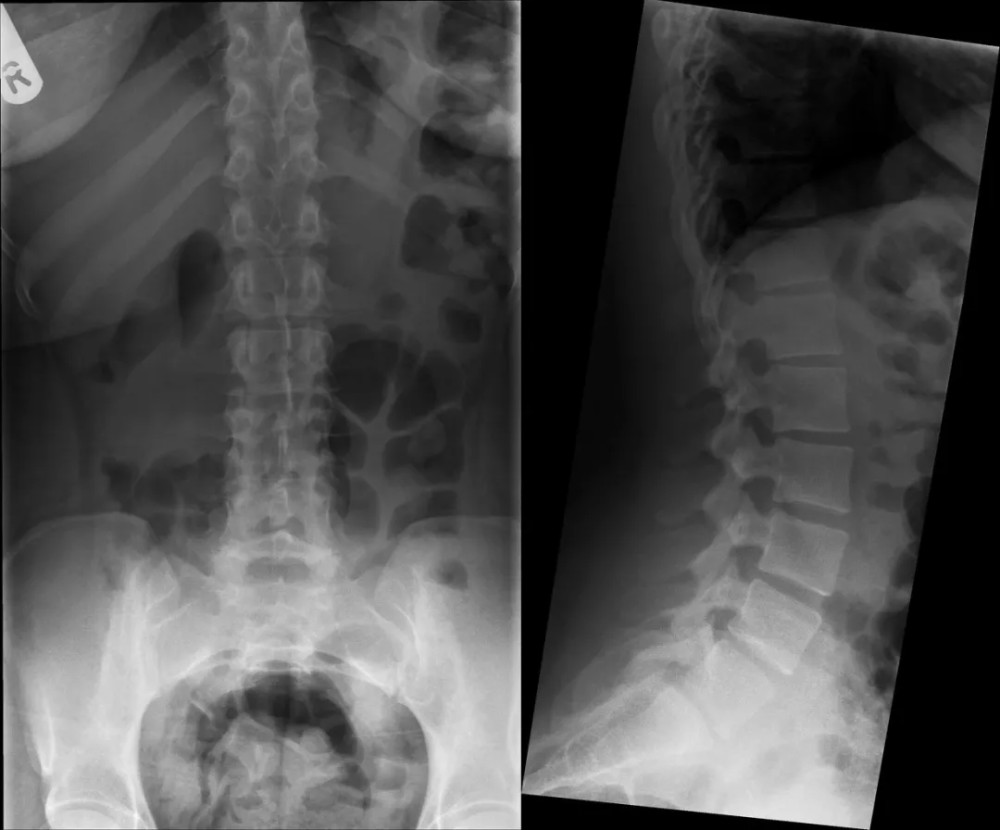

文章插图

右侧 L5 横突肥大 , 故可以诊断为移行椎 Ⅰa 型;

CT 图像重建证实 L5 椎体右侧横突肥大 , 间隙正常 。

腰椎正位片示:L5 椎体双侧横突肥大 , 为Ⅰb 型;